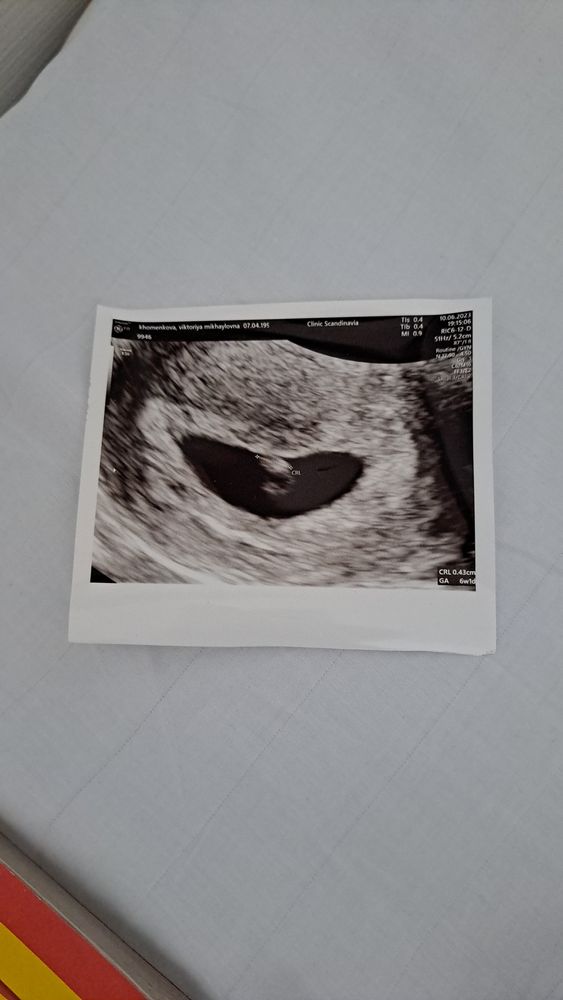

Добрый день. У меня сегодня 25 дпп, постоянно тянет живот, папаверин свечи , ношпа не помогают, лежу в больнице, дают Галакси, он снимает боль, но не надолго. Сделали узи, отслоек и гематом не видят, в больнице так как мазало темным, потом немножко розовым по узи ничего не видят плохо, единственное тонус... Поставили 6 недель+1 день акушерских, перенос был 17 мая крио на згт.... СБ + 117 УДАРОВ, желточный мешочек определяется, срел:3,5 мм, КТО: 4,3 мм